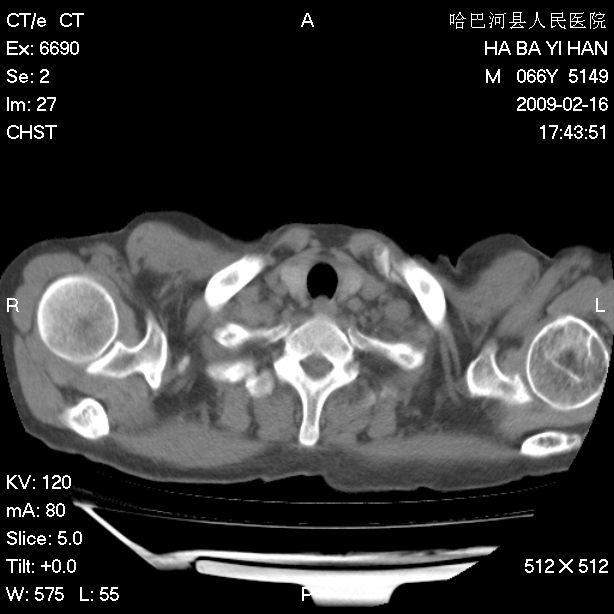

以下是引用huangxun4321在2009-2-16 20:18:00的发言:[br]部分病灶可见硬化边,部分可见骨质破坏消失,部分病灶内可见骨脊,说明病灶内既有良性病变,又有恶性病变,考虑骨巨细胞瘤恶变,未除骨纤恶变,畸形性骨炎少见,亦要考虑.

以下是引用731208在2009-2-16 20:31:00的发言:[br]考虑恶性胸膜间皮瘤并肋骨,脊柱转移。

以下是引用yijiansheng在2009-2-16 20:16:00的发言:[br]考虑恶性胸膜间皮瘤并肋骨,脊柱转移。

以下是引用形影不离在2009-2-16 19:55:00的发言:[br]考虑多发性转移瘤。